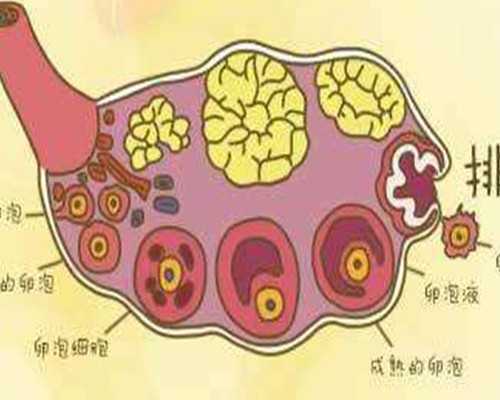

寶雞市生殖醫(yī)學(xué)中心的主要業(yè)務(wù)是男女不孕癥、性功能障礙、習(xí)慣性流產(chǎn)、性傳播疾病、急慢性生殖道炎癥、生殖內(nèi)分泌疾病的診斷和治療,率先采用中西醫(yī)結(jié)合的診斷和治療方法,包括宮腔鏡診斷和治療、輸卵管碘油、B超造影、多功能盆腔治療、卵泡監(jiān)測、人工授精、體外受精超排卵技術(shù);男性生育能力評價、男性前列腺炎、男性不育和性功能障礙檢測和康復(fù)治療、前列腺綜合治療、睪丸附睪穿刺和睪丸活組織檢查以及生殖器驕傲生物、包莖、隱藏陰莖、早泄等特色診療項目的手術(shù)治療,每年門診人數(shù)超過5萬人。